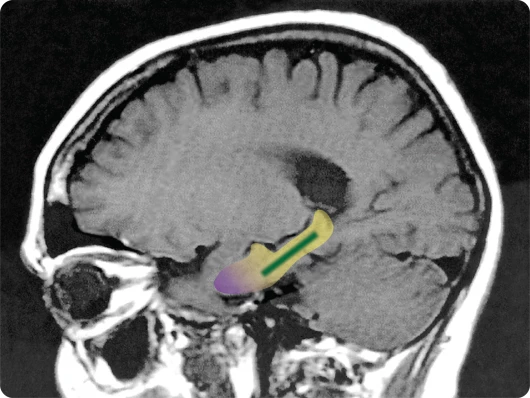

FMRI brain imaging showed that participants on the high-flavanol diet exhibited noticeable improvements in memory in the part of the brain associated with normal age related memory decline, the dentate gyrus. This is a different part of the hippocampus to that affected by early stage Alheimer's disease, the entorhinal cortex.